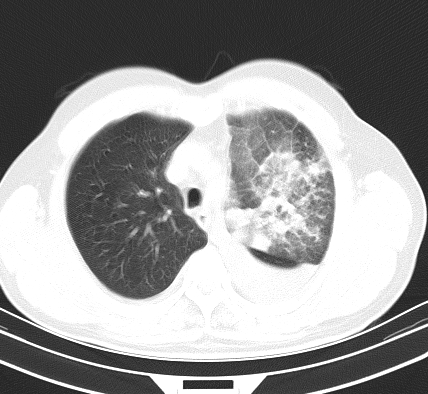

以下是引用老爱克斯新网客在2008-7-31 6:30:00的发言:[br]左肺上叶大片状病灶,左肺上叶支气管狭窄呈鼠尾状,左肺门增大,纵隔内见肿大淋巴结,左侧胸腔积液,余肺清晰。左肺中心型肺癌淋巴结转移,

以下是引用zjb在2008-7-31 6:32:00的发言:[br]左侧中心性肺癌 阻塞性肺炎 肺不张 胸腔积液 建议气管镜

以下是引用zjzjr在2008-7-31 8:45:00的发言:[br]考虑左侧中心性肺癌伴阻塞性肺炎,左肺上叶肺不张,纵隔淋巴结转移;左侧胸腔积液。建议行纤支镜检查。

以下是引用sdzyy在2008-7-31 8:47:00的发言:[br]病灶较治疗前有所进展,胸水增多, 左侧中心性肺癌 并 阻塞性肺炎 肺不张 胸腔积液 可能性大; 建议气管镜检查。 [br] [br]